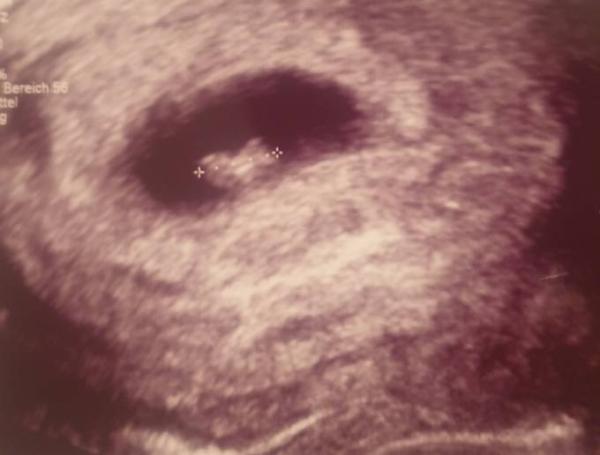

Alles war super mann konnte auch schon den Herzschlag sehen Et ist der 1.7.Füge ein Bild bei

Bild zu Zurück vom FA - Forum für Juli - Mamis

Das ist aber ein schöner Schnappschuss geworden, finde ich. Sieht schon fast gar nicht mehr nach nur einem Zellhaufen aus.